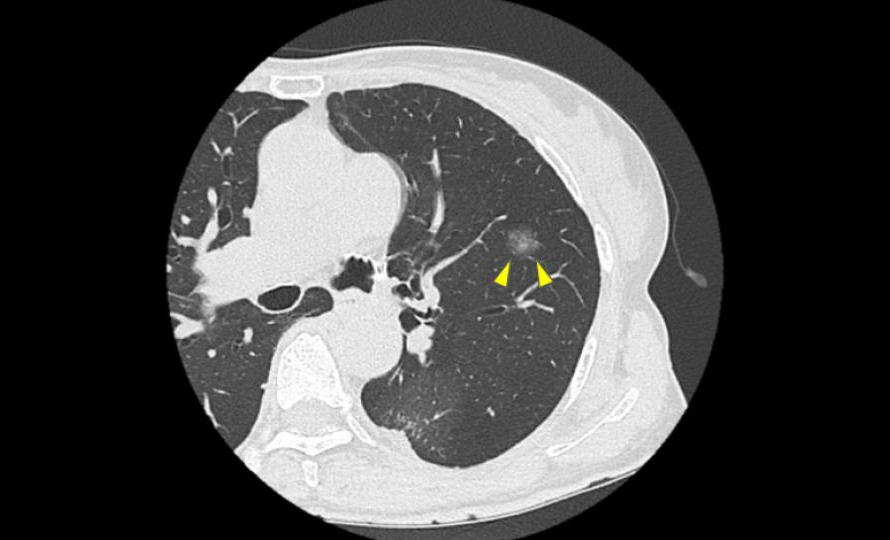

5. 図1.2 のように“早期に見つかる影”で多い相談

図1

図2

近年はCTで、症状が出る前の小さな影が見つかることが増えています。というより、初期の肺がんでは症状が出ないことが多いです。この段階では「すぐ治療」ではなく「まずはCTで経過観察」と言われることも珍しくありません。

ちなみに、先ほど示した図1、2に関しては手術を行い、病理検査の結果いずれも「肺癌」と診断されました。